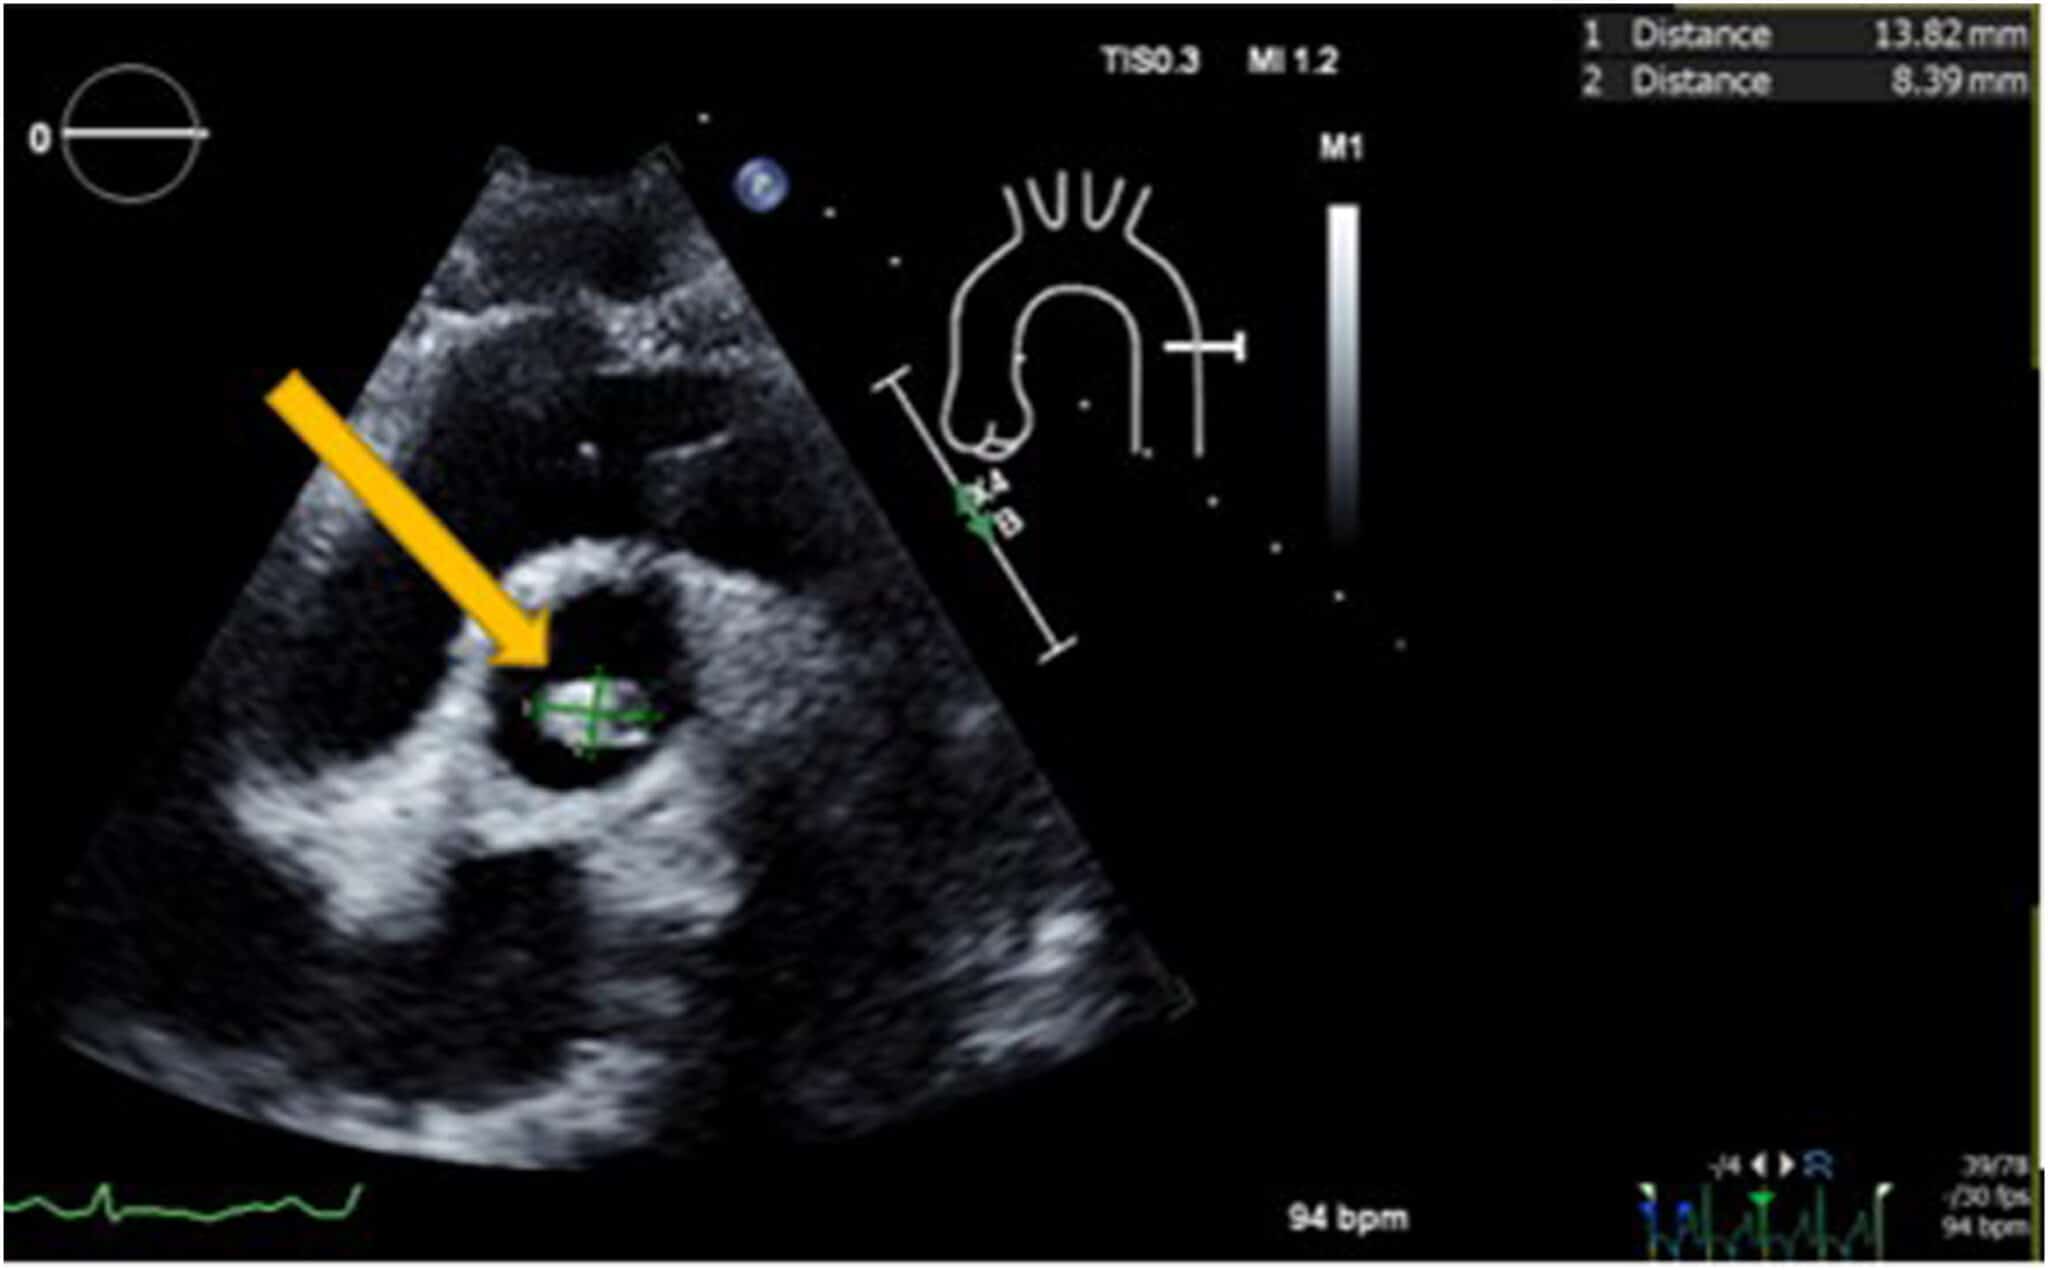

Imágenes del ecocardiograma. 1) Ecocardiografía transtorácica. Plano Tapse Ecocardiografia 141 rows el desplazamiento sistólico del plano del anillo tricuspídeo (siglas en inglés, tapse) es una medida ecocardiográfica que. Aunque únicamente evalúa la contracción longitudinal del vd, ha demostrado una buena correlación con otras medidas que evalúan la función sistólica global. el tapse (desplazamiento longitudinal del anillo tricúspide) continúa siendo una forma habitual y sencilla de cuantificar la. Tapse Ecocardiografia.

Diagnóstico y estudio de cardiopatías infrecuentes multimodalidad Tapse Ecocardiografia Rvot, pulmonary valve, and pa 41 b. el tapse (desplazamiento longitudinal del anillo tricúspide) continúa siendo una forma habitual y sencilla de cuantificar la función del vd. Aunque únicamente evalúa la contracción longitudinal del vd, ha demostrado una buena correlación con otras medidas que evalúan la función sistólica global. 141 rows el desplazamiento sistólico del plano del anillo. Tapse Ecocardiografia.